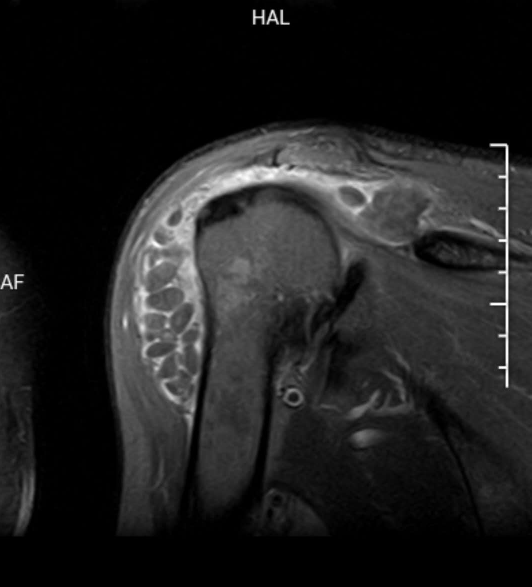

X 线检查无特殊意义,以 MRI 检查最为敏感,关节周围软组织可见不同程度水肿,肩峰下可见积液,以及大量直径不等(1 ~ 10 mm)的类圆形占位,与周围肌肉组织相比呈等 T1 稍长 T2 信号。

无明显症状的关节病,米粒体滑囊炎会被忽略漏诊。主要需与色素沉着绒毛结节性滑膜炎 (PVNS) 和滑膜软骨瘤相鉴别。鉴别诊断要点主要以 MRI 为主。

化生软骨往往呈叶状,未钙化时的 T1 像为等信号,T2 加权像为高信号;已经钙化的则 T1 和 T2 加权像均为高信号。